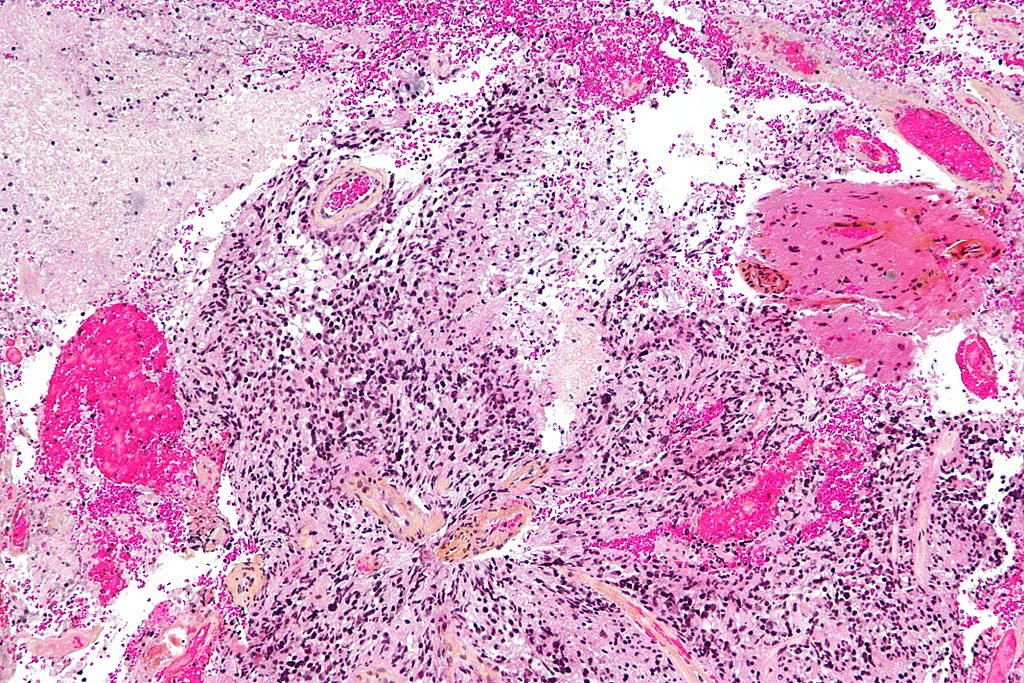

Η ανακάλυψη θα μπορούσε να ωφελήσει τους 2.500 ανθρώπους ετησίως στο Ηνωμένο Βασίλειο που διαγιγνώσκονται με γλοιοβλάστωμα, την πιο κοινή μορφή καρκίνου του εγκεφάλου και επίσης μία από τις πιο επιθετικές. Οι άνθρωποι με τη νόσο ζουν κατά μέσο όρο μόλις 12-18 μήνες μετά τη διάγνωση, ενώ ορισμένοι ακόμη λιγότερο.

Το εμβόλιο είναι μια μορφή ανοσοθεραπείας, κατά την οποία το ανοσοποιητικό σύστημα του οργανισμού προγραμματίζεται να εντοπίζει και να επιτίθεται στον όγκο. Είναι το πρώτο που αναπτύχθηκε για την αντιμετώπιση των όγκων του εγκεφάλου.